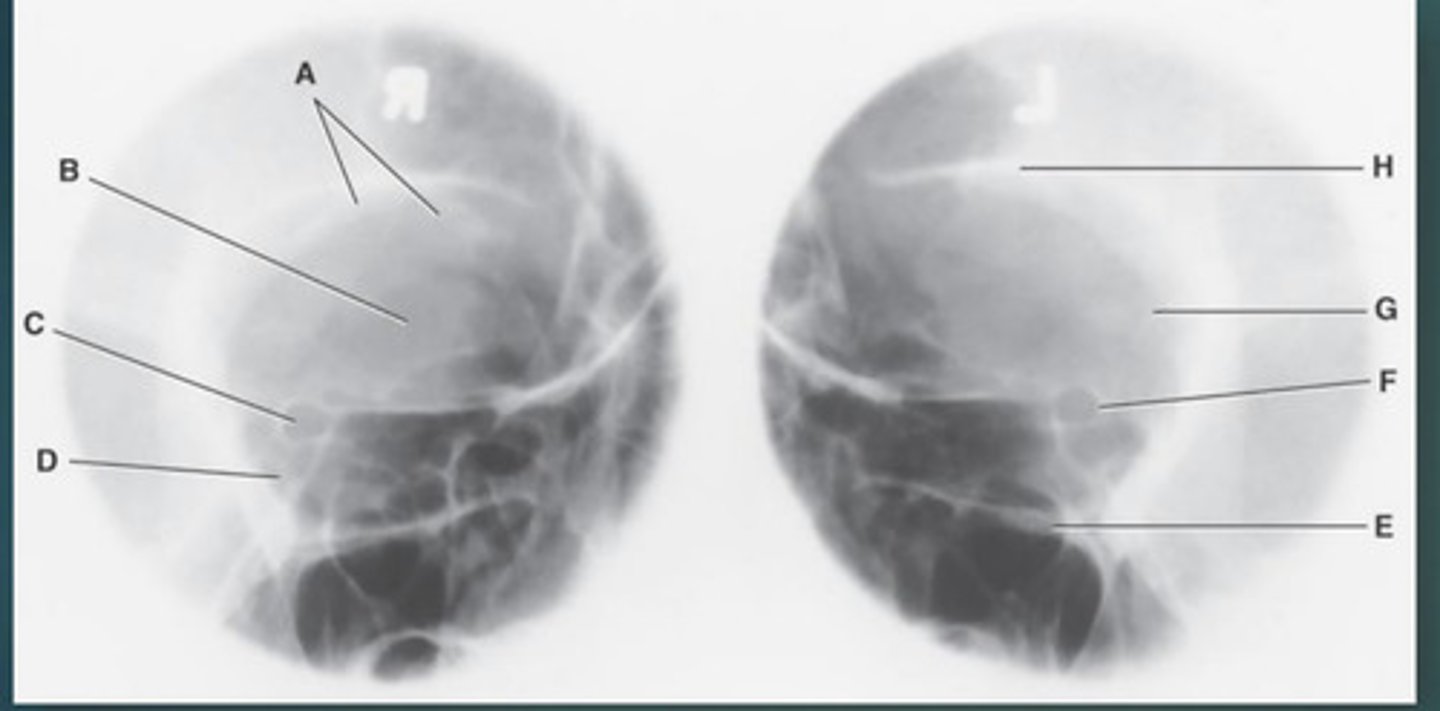

Lateral sinus

What position?

L. Orbital roofs

A.

L. Greater wings of sphenoid

B.

sella turcica of sphenoid

C.

L. Sphenoid sinus

D.

L. Rami of mandible

E.

L. Maxillary sinuses

F.

L. Ethmoid sinuses

G.

L. Frontal sinuses of frontal bone

H.